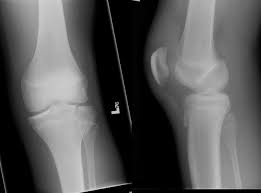

medial meniscus

cartilage in the knee between the femoral condyle and the medial tibial plateau

lateral meniscus

cartilage in the knee between the lateral femoral condyle and the lateral tibial plateau

lateral collateral ligamant

runs from the femur to the fibula

medial collateral ligament

attaches the femur to the tibia

anterior cruciate ligament

ligament in the knee that attaches to the anterior tibial and connects to the posterior femur

posterior cruciate ligament

attaches posterior tibia and attaches to the anterior femur